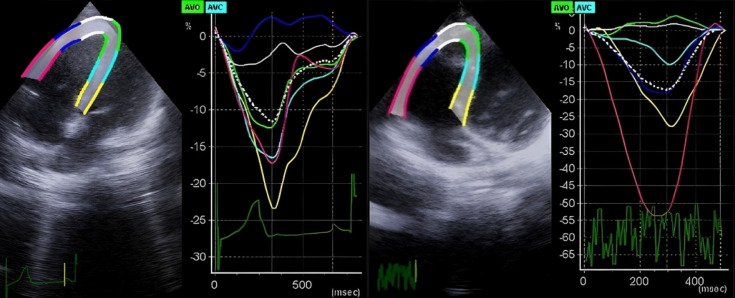

Background: Balloon Pulmonary Valvuloplasty (BPV) is a procedure for Pulmonary Stenosis (PS) treatment. In this study, right ventricle (RV) performance was determined through 2D-Speckle Tracking Echocardiography (2D-STE).

Methods: The study involved 25 diagnosed children with PS undergoing BPV and 25 normal children. They were examined using 2D-STE and Linear Mixed Model (LMM) approach was used to determine changes in Pulmonary Valve Peak Gradient (PVPG), Tricuspid Annular Plane Systolic Excursion (TAPSE), strain and Strain Rate (SR) for RV, and Ejection Fraction for Left Ventricle (LVEF).

背景:球囊肺动脉瓣成形术(BPV)是治疗肺动脉狭窄(PS)的一种方法。本研究通过二维斑点追踪超声心动图(2D-STE)确定右心室(RV)的性能:研究涉及 25 名确诊为 PS 并接受 BPV 治疗的儿童和 25 名正常儿童。研究使用二维啄木鸟跟踪超声心动图(2D-STE)和线性混合模型(LMM)方法对他们进行检查,以确定肺动脉瓣峰值阶差(PVPG)、三尖瓣环平面收缩期偏移(TAPSE)、左心室应变和应变率(SR)以及左心室射血分数(LVEF)的变化:两组在 TAPSE(P=0.001)、整体应变(P=0.001)、室间隔顶端应变(P=0.024)、室间隔中部应变(P=0.001)、室间隔基底应变(P=0.001)、室间隔顶端侧 SR(P=0.001)、室间隔中部侧 SR(P=0.007)、室间隔基底侧 SR(P=0.001)和室间隔顶端 SR(P=0.001)方面存在显著差异。BPV 后,LVEF(P=0.001)和 TAPSE(P=0.001)增加,但 PVPG 下降(P=0.001)。BPV 后,观察到心尖外侧应变(P=0.004)、室间隔中部应变(P=0.001)、心尖室间隔应变(P=0.003)、室间隔中部应变(P=0.001)、室间隔基底应变(P=0.048)、心尖室间隔 SR(P=0.025)和室间隔中部 SR(P=0.023)增加。性别与基底侧应变(P=0.019)、中隔应变(P=0.037)和中隔SR(P=0.020)的平均变化显著相关。PS患儿的年龄与基底室间隔应变(P=0.031)和基底室间隔SR(P=0.018)的平均变化有关:结论:PS患儿室间隔应变和SR在BPV术后有所改善。儿童的性别和年龄对 BPV 后 RV 应变和 SR 变化有显著影响。